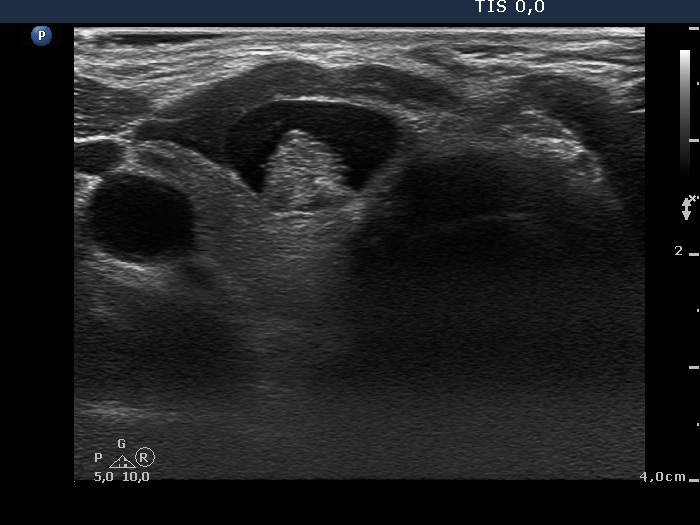

Benign cystic nodule (cytology and wash-out) - case 2177

Longitudinal scan

According to the EU-TIRADS, this lesion cannot be regarded as a purely cystic nodule due to the presence of wall-thickening (yellow arrows). The EU-TIRADS defines this lesion as an EU-TIRADS 3 nodule.